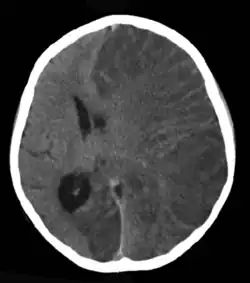

Estima-se que o traumatismo cranioencefálico (TCE) seja responsável por 6% a 20% dos casos de epilepsia, dependendo da gravidade, mecanismo e população estudada. Lesões cerebrais leves dobram o risco, enquanto TCEs graves aumentam o risco em cerca de sete vezes. Em vítimas de ferimento craniano por arma de fogo de alta energia, o risco pode chegar a 50%.[58] O AVC é uma causa importante de epilepsia, especialmente em adultos mais velhos.[59] Aproximadamente 6% a 10% das pessoas que sofrem um AVC desenvolvem epilepsia, geralmente nos primeiros anos após o evento. O risco é mais alto em AVCs graves que envolvem regiões corticais, especialmente nas hemorragias intracerebrais.[60] Entre aqueles com tumores cerebrais, quase 30% têm epilepsia, tornando-os a causa de cerca de 4% dos casos. O risco é maior para tumores no lobo temporal e aqueles que crescem lentamente.[61]

A neuroimagem, geralmente por ressonância magnética (RM), é recomendada para investigar causas estruturais da epilepsia. Quando a RM for contraindicada ou indisponível, pode-se considerar a tomografia computadorizada (TC). A interpretação deve ser feita por radiologistas com experiência em epilepsia.[80]